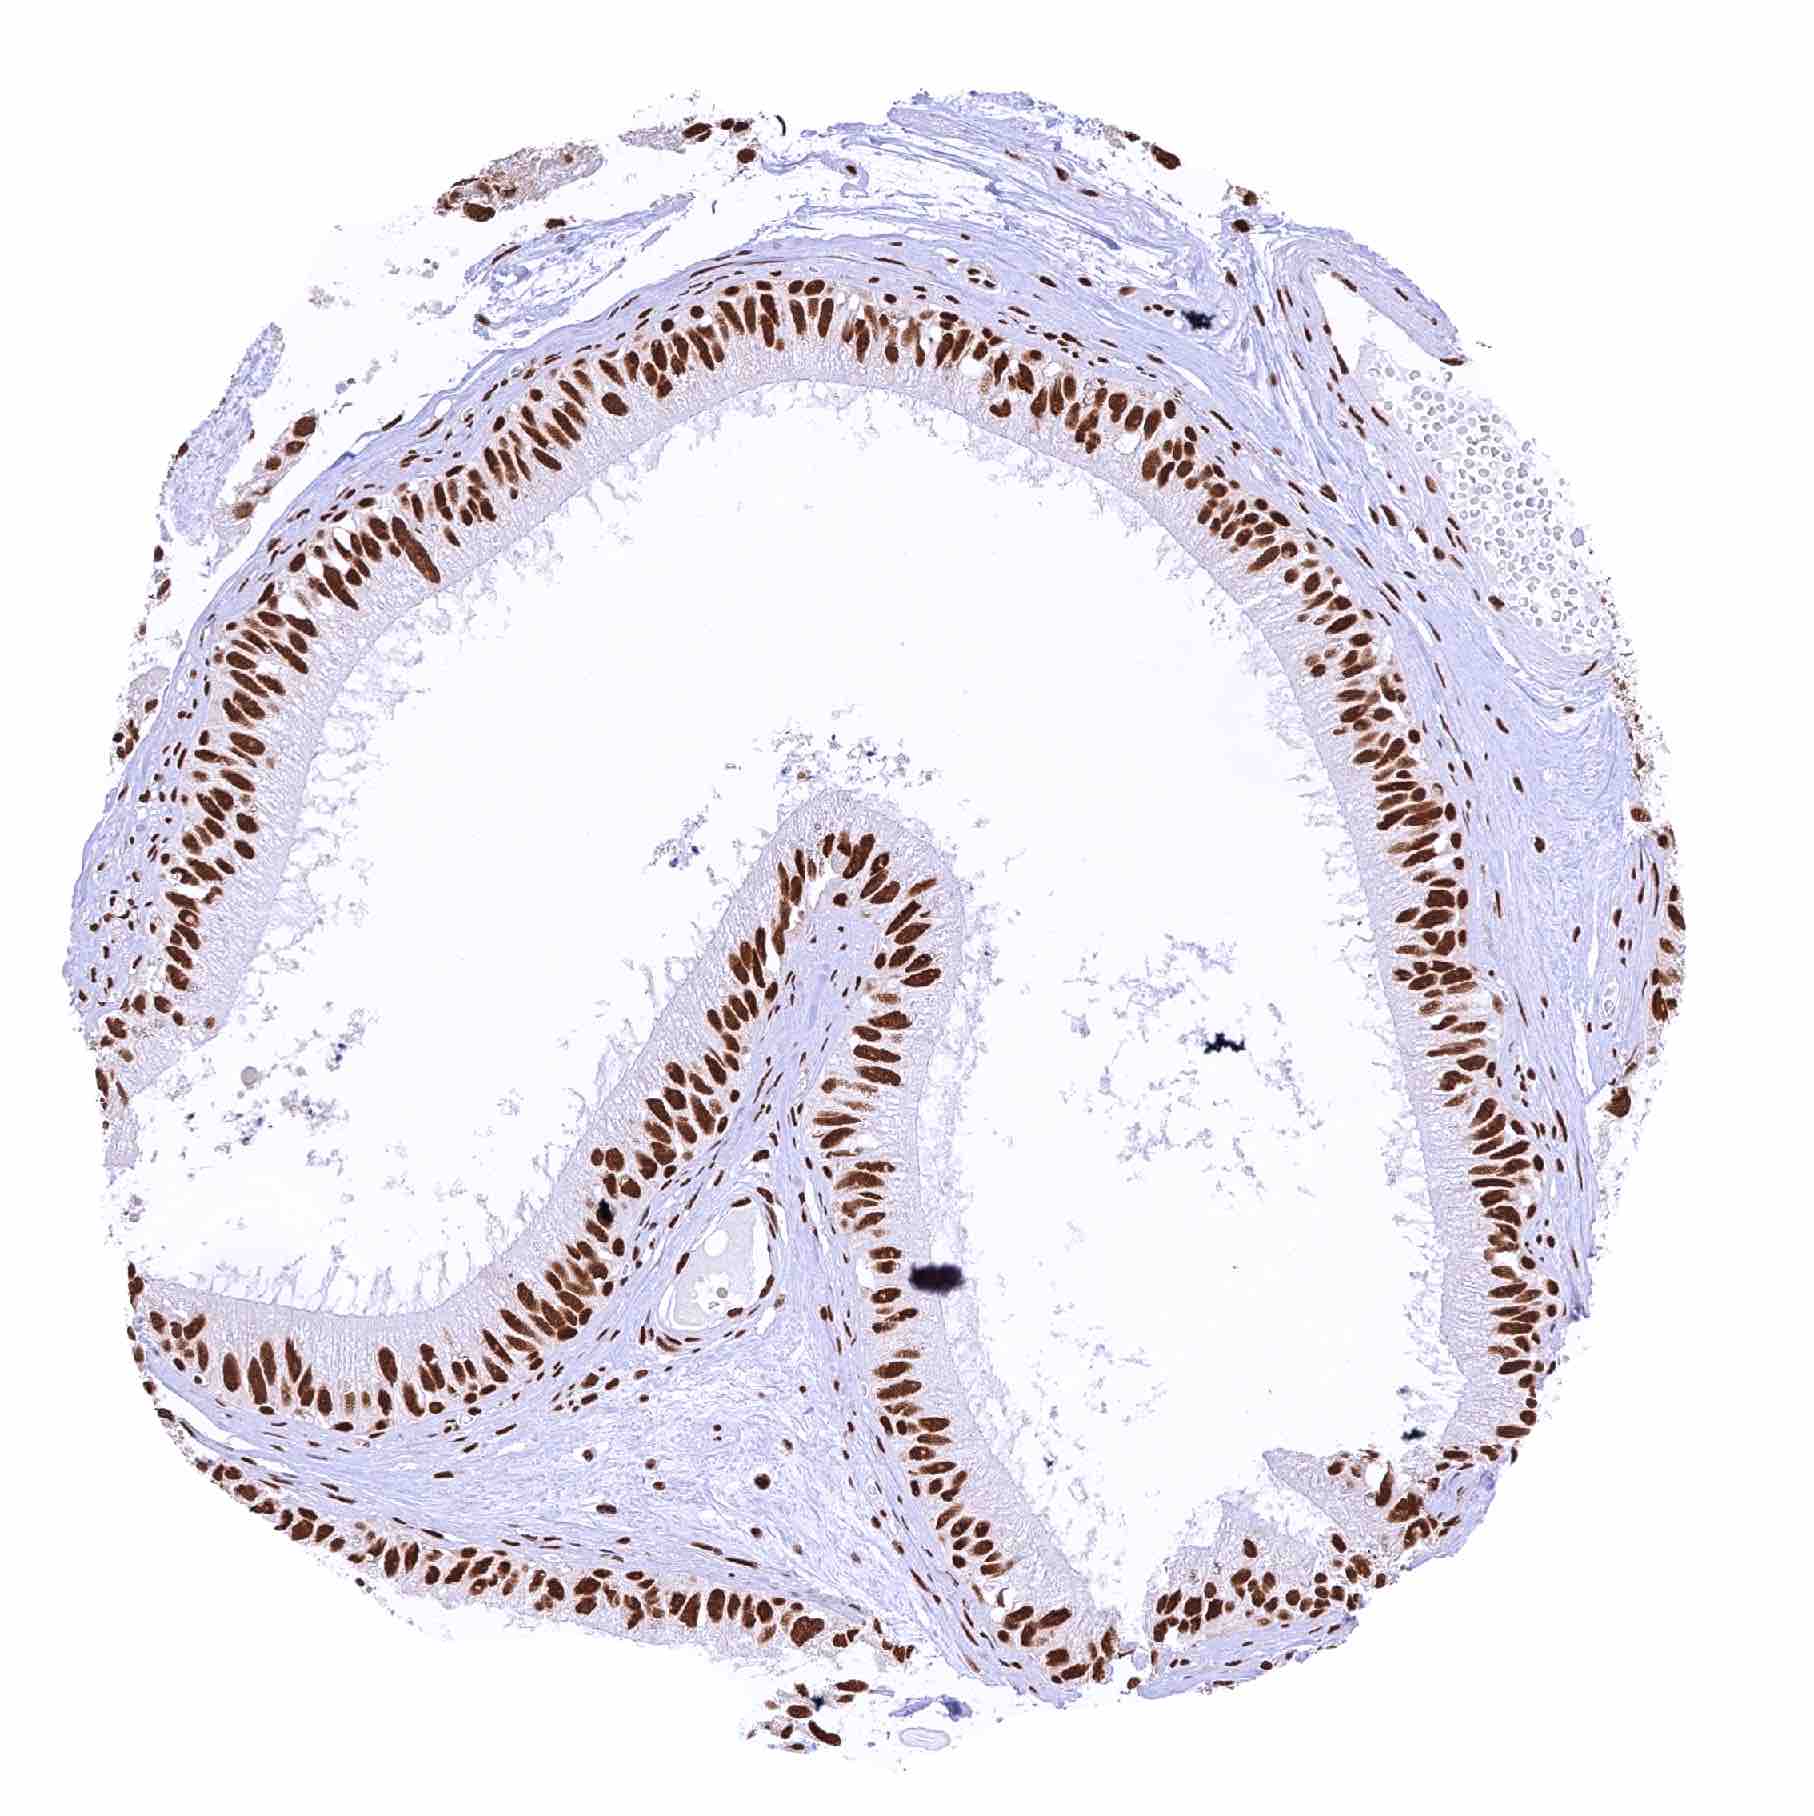

Colon descendens, mucosa – Distinct nuclear MRE11 staining of all cells. Slight but significant decrease of MRE11 staining from the crypt baseto the superficial epithelial cell layers